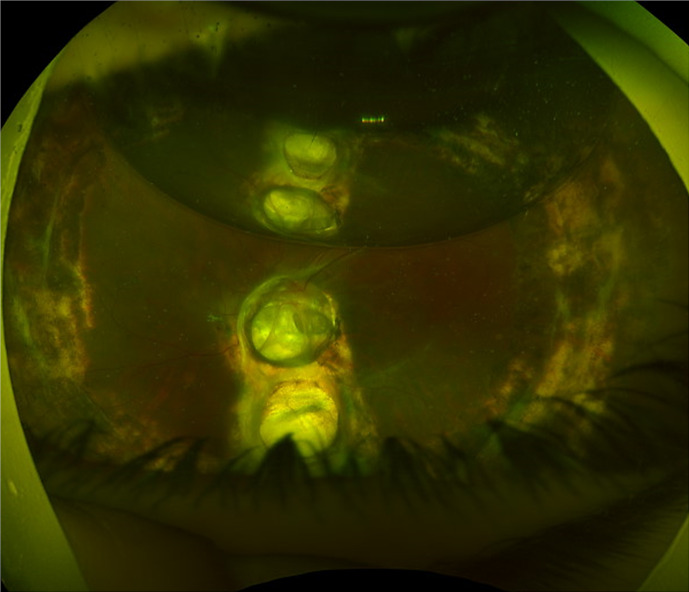

Case presentation: A 15-year-old male with a history of left eye congenital optic disc coloboma and amblyopia presented with a third recurrence of retinal detachment (RD) with proliferative vitreoretinopathy. The patient underwent PPV, subretinal fluid drainage through a peripheral retinotomy, silicone oil tamponade, and endolaser around the coloboma and retinotomy. The retina re-attached successfully. However, 14 months postoperatively examination revealed high intraocular pressure (IOP) of 33 mm Hg and a sub-macular bubble of silicone oil was evident. The patient underwent sub-macular silicone oil removal.

Conclusion: Here we describe the unique late-onset subretinal migration of intravitreal silicone oil following RD repair in an eye with optic disc coloboma in association with raised IOP. This case demonstrates potential mechanisms of subretinal silicone oil migration through the coloboma that serves as a passage and an increased IOP, which drives the oil from the vitreous to the subretinal space.